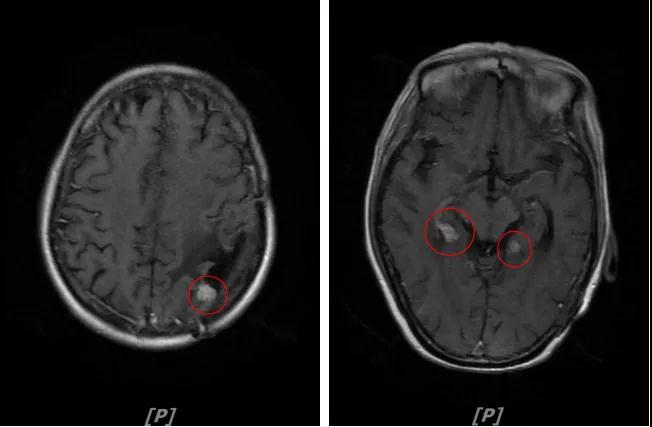

b.2014年3月全脑放疗结束后,予以LX方案治疗(拉帕替尼 1250mg qd+卡培他滨 1500mg bid)。每3个月规律复查,未见明显异常。下图为2014年6月患者行头颅增强MR检查,提示左顶叶脑转移瘤术后改变。

每3个月规律复查,未见明显异常。如2015年8月 头颅MR检查,提示:左顶叶脑转移瘤术后放疗后改变,对比前片2015年3月10日相仿。